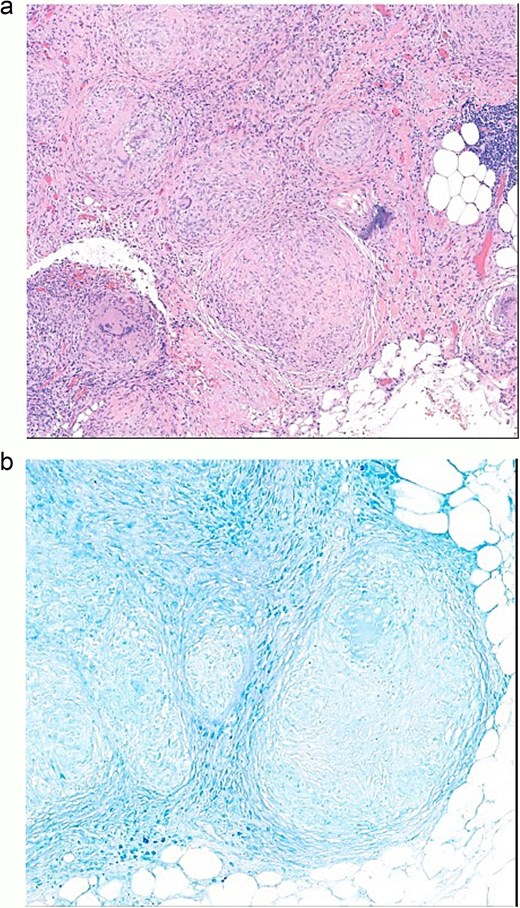

Cytology examination showed no malignant cells. Subsequent pathological examination demonstrated non-necrotizing granulomatous inflammation (Fig. 3a). Special staining, including Periodic Acid-Schiff (PAS), Gomori Methenamine Silver (GMS), and acid-fast stains, was performed, but neither fungal elements nor acid-fast bacilli were identified (Fig. 3b).

(a) Omentum pathology, non-necrotizing granulomatous inflammation. (b) Omentum pathology diagnosis, acid-fast stain negative.